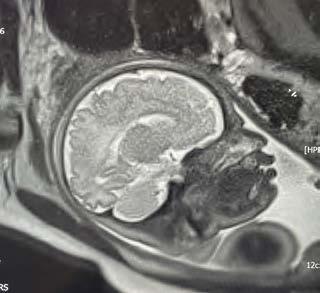

When an unborn baby has an abnormality, decisions about the delivery and neonatal care can often be planned in advance – with the help of an MRI.

MRI image acquisition can be tricky and quality reporting is an acquired skill. An expert in the field, Dr Lauren Raubenheimer honed her skills in London under world-renowned foetal and neonatal imaging specialist, Prof Mary Rutherford. Dr Raubenheimer joined SCP Radiology as a consulting radiologist.

“When a couple discovers their baby has an abnormality, the impact is enormous,” she explains. “I hope my findings give parents more answers as they navigate a difficult path.” With the help of an MRI, Dr Raubenheimer says that in many cases, the timing and route of delivery, as well as the neonatal care required, can be planned in advance.

Specialists after an abnormality has been detected on a screening ultrasound. An MRI can be done to confirm the abnormality, as well as to assess for abnormalities that are not readily visible through standard imaging techniques. This can significantly affect the prognosis. A foetal MRI can be performed either in the second or third trimester.

Dr Raubenheimer’s special interest is in developmental foetal brain abnormalities, but she also performs MRIs for body abnormalities, including congenital diaphragmatic hernia and spina bifida.

MRI can be superior to ultrasound in certain instances, such as assessing the folding of the brain and parts of the brain obscured by the skull, when amniotic fluid is low and when mothers have a high body mass index (BMI).

Foetal movement used to be an obstacle in getting good quality MR images. However, with today’s advanced magnets and faster imaging sequences, excellent image quality can be obtained. At SCP Radiology, foetal MRI scans are done exclusively by lead MRI radiographer Andrea Nagel.

Safety is, of course, of utmost importance. Dr Raubenheimer reassures us that present data shows no conclusively documented harmful effects of MRI imaging on the

developing foetus, providing it is at the safe and optimal level. She also adds that MRI does not use ionising radiation, and intravenous contrast is not administered in foetal MRI.

Foetal MRI is covered by medical aids, but pre-authorisation is required.

Dr Raubenheimer prefers that patients are referred from a Foetal Medicine Specialist after a detailed ultrasound. “Having access to ultrasound reports and knowing the exact gestation is crucial to an accurate MRI report,” she emphasises.